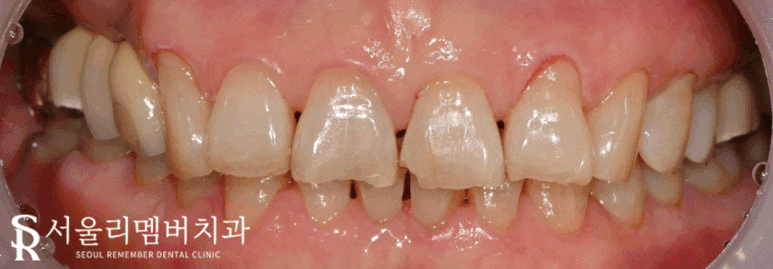

리멤버에서는

방습, 본딩, 충전, 폴리싱 등 차차 과정을 거쳐

군데군데 드러나 있던 곳들을 틈이 보이지 않도록 올려드렸습니다.

이 과정은 술자의 기술력에 의해 결과 차이가 확연히 드러나는 치료인데요.

한 땀 한 땀 올려가며 형태를 잡는 방식으로 진행되기 때문에

과잉되거나 모자란 경우에는 또 다른 문제가 생길 수 있습니다.

또한 치경부는 오목한 부위에 메꿔 넣는 것이 아닌,

평평한 부위에 올려드리기 때문에 접착이 잘될 수 있도록 더! 신경을 써야 됩니다.

실제로 이 환자께서도

음식 찌꺼기가 자주 끼는 등의 불편함이 싹 사라지셨다는데요.

만족할 만한 결과를 안겨드릴 수 있어서 다행이네요^^